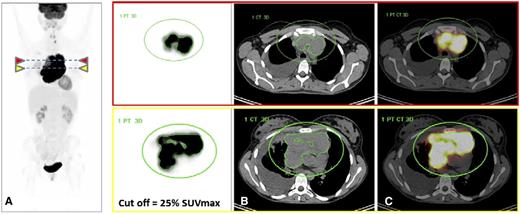

FDG-PET/CT images from a 25-year-old woman with PMBCL who progressed and died under treatment with R-MACOP-B. (A) FDG-PET images (maximum intensity projection view and transverse slices at 2 different levels) demonstrate high FDG uptake in a bulky mediastinal mass; the green circle defines a volume of interest where the MTV is automatically segmented with a 25% SUVmax threshold. MTV limits are displayed in green around the mediastinal tumor. SUVmax = 29; TLG = 6706, falling in the high-risk category. (B) CT with the projections of the MTV contours segmented on FDG-PET. (C) Fused FDG-PET and CT images. Courtesy of Dr Luca Ceriani.

However, although the prognostic values of interim or eot-PET have been extensively studied in lymphoma, the role of quantitative data derived from baseline PET has been investigated less due to technical limitations. In HL, DLBCL, and T-cell lymphoma, prognostic values of baseline metabolic tumor volume (MTV) and TLG have been reported only on the basis of retrospective series.5 Ceriani et al report on the first study prospectively exploring the value of quantitative PET in aggressive lymphoma, focusing on 103 PMBCL patients. Maximum standardized uptake value (SUVmax), MTV, and TLG, all parameters dependent on lymphoma metabolism, measured on baseline FDG-PET/CT were negative prognostic factors for PFS and overall survival (OS). A higher risk of progression or deaths was associated with an MTV and TLG increase, but TLG was the strongest predictor of outcome independent of the stage of the disease. Long-term outcome was significantly better for patients with low TLG (less than the cutoff value) than for those with high TLG (greater than the cutoff value) with a 5-year OS of 100% vs 80% and 5-year PFS of 99% vs 64%, respectively. The method based on a percent thresholding of the tumor SUVmax was easy to use and reproducible (see figure). The technical difficulties of quantitative PET were minimized in PMBCL because tumor burden is mainly limited to a single bulky mass, which gives strength to the results of this study.